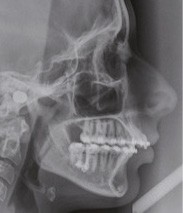

Nous avons pu repositionner l’incisive mandibulaire de 8° (fig. 10), obtenir un surplomb correspondant à la classe II d’Angle et ainsi réaliser l’avancée mandibulaire. Le chirurgien accompagne celle-ci d’une génioplastie afin d’harmoniser le profil. Nous corrigeons la DDD par stripping des incisives mandibulaires ce qui permet de corriger encore de 1° l’axe incisif.

Le résultat de fin de traitement est satisfaisant. Le profil de la patiente est harmonisé. Une contention fixe mandibulaire et maxillaire de canine à canine est choisie.

À propos du cas, on note la persistance d’une petite classe II squelettique (ANB = 5°). Cependant, l’axe de l’incisive maxillaire ne permet pas une correction plus importante de la classe II par avancée mandibulaire car le surplomb est déjà faible et l’incisive maxillaire est légèrement versée (106°). Les axes de 11 et 12 auraient pu être améliorés.